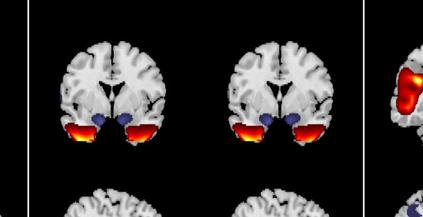

In the last two decades, unsupervised latent variable models---blind source separation (BSS) especially---have enjoyed a strong reputation for the interpretable features they produce. Seldom do these models combine the rich diversity of information available in multiple datasets. Multidatasets, on the other hand, yield joint solutions otherwise unavailable in isolation, with a potential for pivotal insights into complex systems. To take advantage of the complex multidimensional subspace structures that capture underlying modes of shared and unique variability across and within datasets, we present a direct, principled approach to multidataset combination. We design a new method called multidataset independent subspace analysis (MISA) that leverages joint information from multiple heterogeneous datasets in a flexible and synergistic fashion. Methodological innovations exploiting the Kotz distribution for subspace modeling in conjunction with a novel combinatorial optimization for evasion of local minima enable MISA to produce a robust generalization of independent component analysis (ICA), independent vector analysis (IVA), and independent subspace analysis (ISA) in a single unified model. We highlight the utility of MISA for multimodal information fusion, including sample-poor regimes and low signal-to-noise ratio scenarios, promoting novel applications in both unimodal and multimodal brain imaging data.